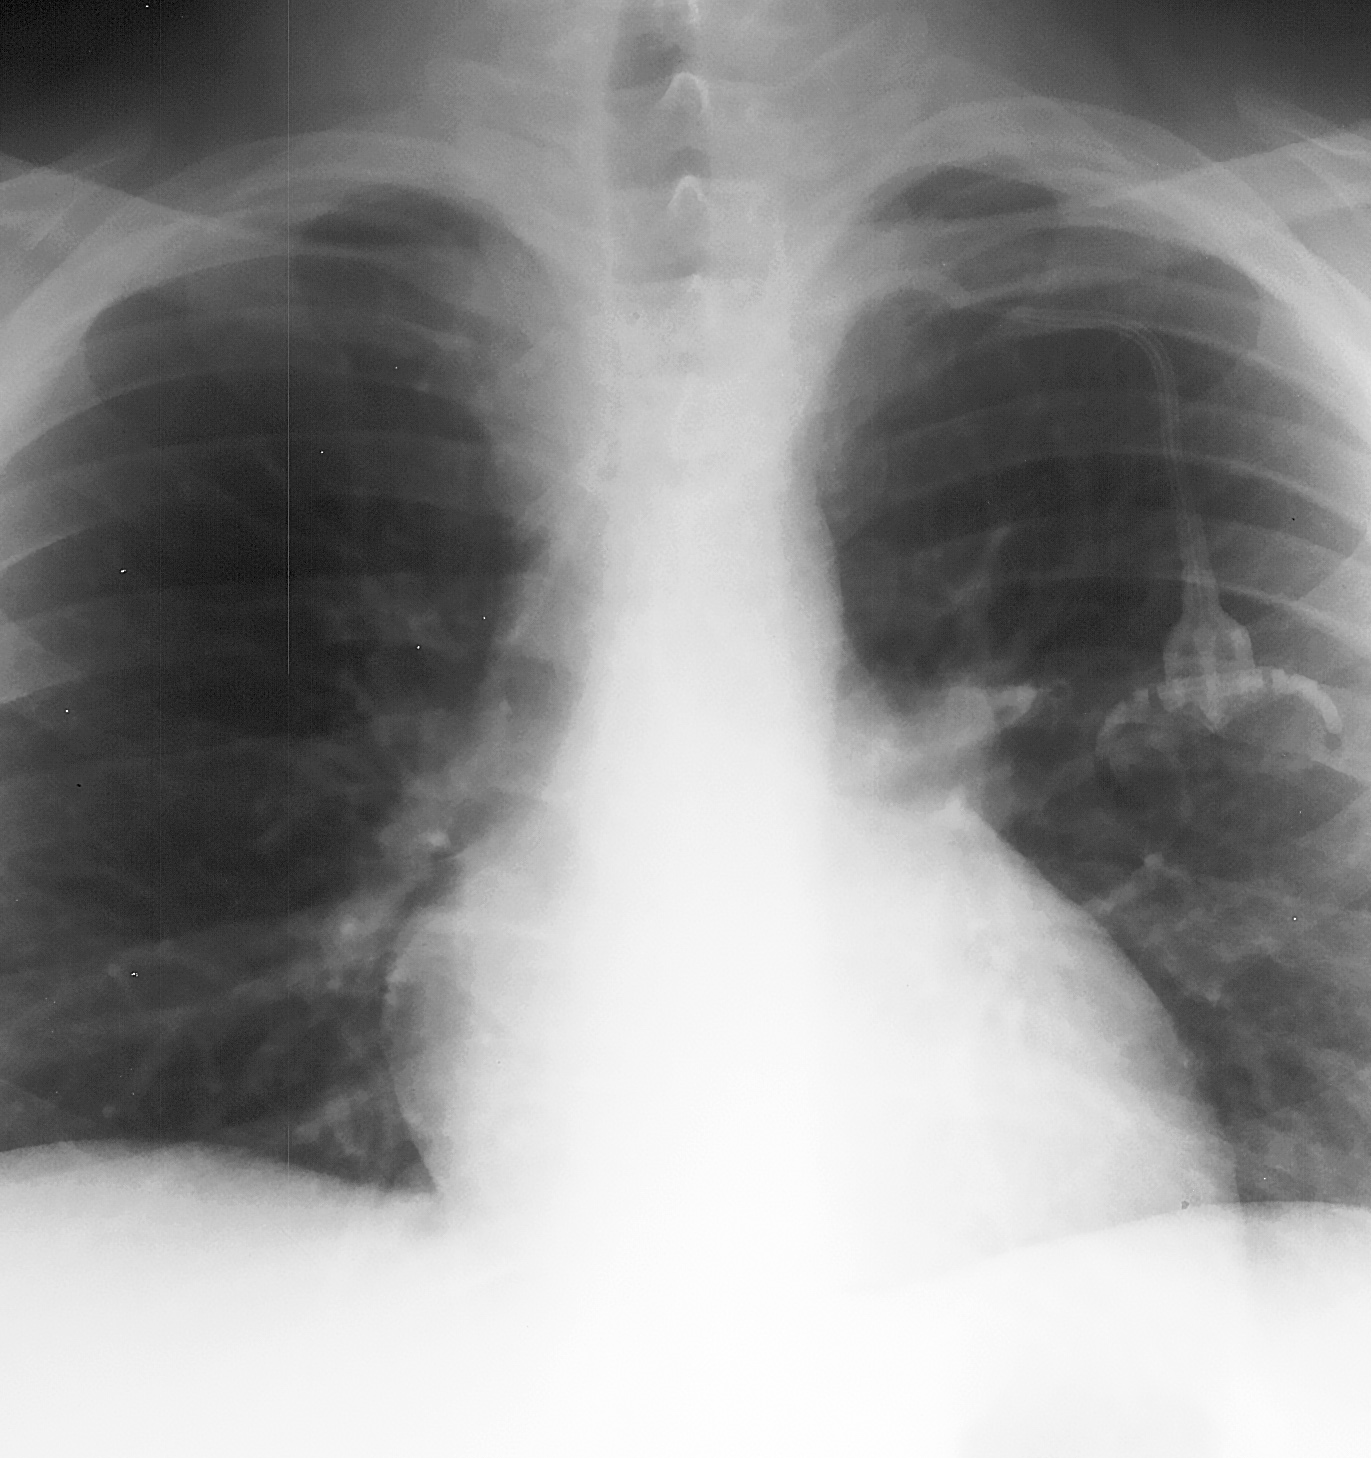

◂Breast Anatomy